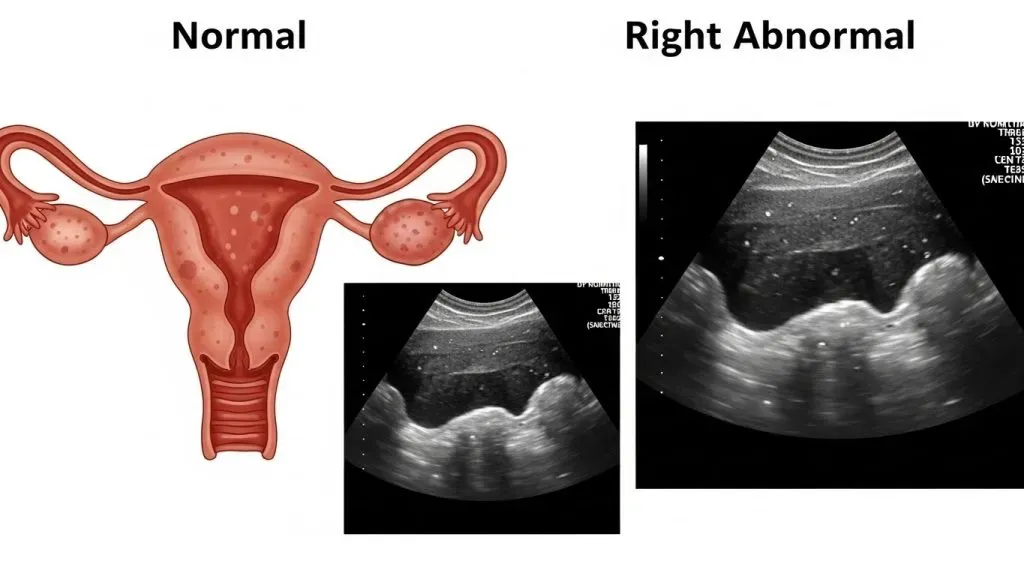

Transvaginal ultrasound (TVUS) is one of the most frequently used imaging tests when clinicians evaluate the uterus and its lining. For patients and clinicians alike, a central question surfaces repeatedly: can endometrial cancer be detected by ultrasound? The short, practical truth is that ultrasound is an excellent triage tool — it identifies suspicious changes such as endometrial thickening, focal masses, or intrauterine fluid — but it does not replace tissue diagnosis.

Yes — ultrasound (especially transvaginal ultrasound, TVUS) can detect signs that may suggest endometrial cancer, such as a thickened uterine lining or a visible mass. However, ultrasound cannot definitively diagnose endometrial cancer. To confirm a diagnosis, a tissue sample (an endometrial biopsy or a hysteroscopy-guided biopsy) is required.

A transvaginal ultrasound (TVUS) uses a small probe inserted into the vagina to send sound waves into the pelvis and create high-resolution images of the uterus, endometrium (uterine lining), and ovaries. Because the probe is closer to the organs, TVUS gives much clearer detail than an abdominal (pelvic) ultrasound.

What TVUS images show (endometrial lining, masses, fluid)?

TVUS images let the sonographer or gynecologist measure:

- Endometrial thickness (in millimetres),

- Focal masses or polyps inside the uterine cavity,

- Fluid in the uterine cavity (sometimes a sign of bleeding or other issues),

- Irregularities of the endometrial surface, and

- Blood flow patterns if Doppler imaging is used.

These visual clues help doctors decide whether further sampling (biopsy) or targeted procedures are needed.

What ultrasound can show about the endometrium?

Ultrasound is a structural test: it shows shape, size, and some functional indicators (like blood flow) — not the microscopic make-up of the tissue. Here’s what it commonly reveals.